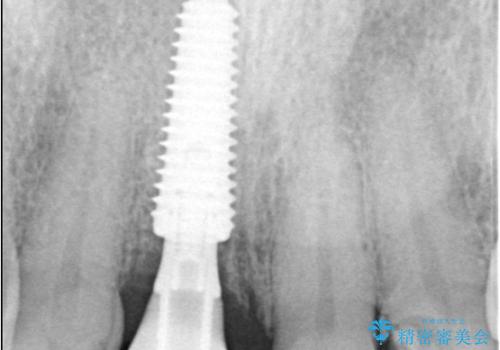

前歯は見た目の印象に大きく関わる部位であるため、できる限り治療期間中の審美性と機能性を損なわないことが求められます。患者さんとも相談のうえ、抜歯と同時にインプラント体を埋入する「即時埋入インプラント」を選択しました。これにより治療期間の短縮と、歯ぐきや骨の形態を保ちながらの審美的回復が可能となります。

治療は、まず感染の原因となっていた前歯を慎重に抜歯し、抜歯と同時にインプラントを埋入しました。審美性を重視する部位であるため、骨や歯ぐきのボリュームを維持するための補填処置も併用しています。術後は仮歯を装着し、見た目を保ちながらインプラントと骨がしっかりと結合するのを待ちました。

約3か月の治癒期間を経て、最終的にセラミックの上部構造を装着。周囲の歯や歯ぐきとの調和を図りながら、自然な見た目としっかりとした噛み心地を再現しました。患者さんからは「折れて落ち込んでいたが、見た目も噛み心地も元通りで嬉しい」とのお声をいただきました。即時埋入により、精神的な負担も少なく治療を終えることができました。